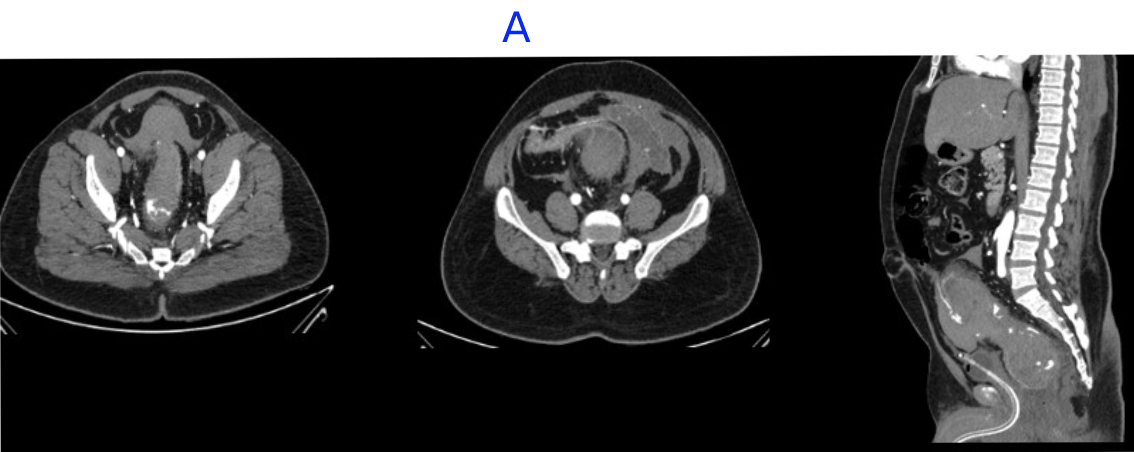

- Large intramural hematoma with significant adjacnet fat starnding noted in rectum and distal sigmoid causing significant luminal narrowing.

- Multiple area of contrast extravasation within the hematoma which shows increase in size in venous and delayed phases with multiple pools of contrast - suggesting active bleeding from branches of inferior mesenteric artery..

- Distal rectum and proximal sigmoid colon mild edematous wall thickening.

- Hemorrhagic fluid noted in bilateral paracolic gutter and pelvis with active contrast extravasation.

- Omentomesenteric fat stranding in lower abdomen with mesorectal fascial thickening noted.